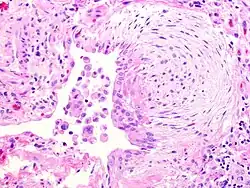

![]() | Vesicular mole | Micrograph of vesicular mole showing oedematous chorionic villus with circumferential proliferation of trophoblasts. | Category: Histopathology of chorionic villi | chorionic villi |